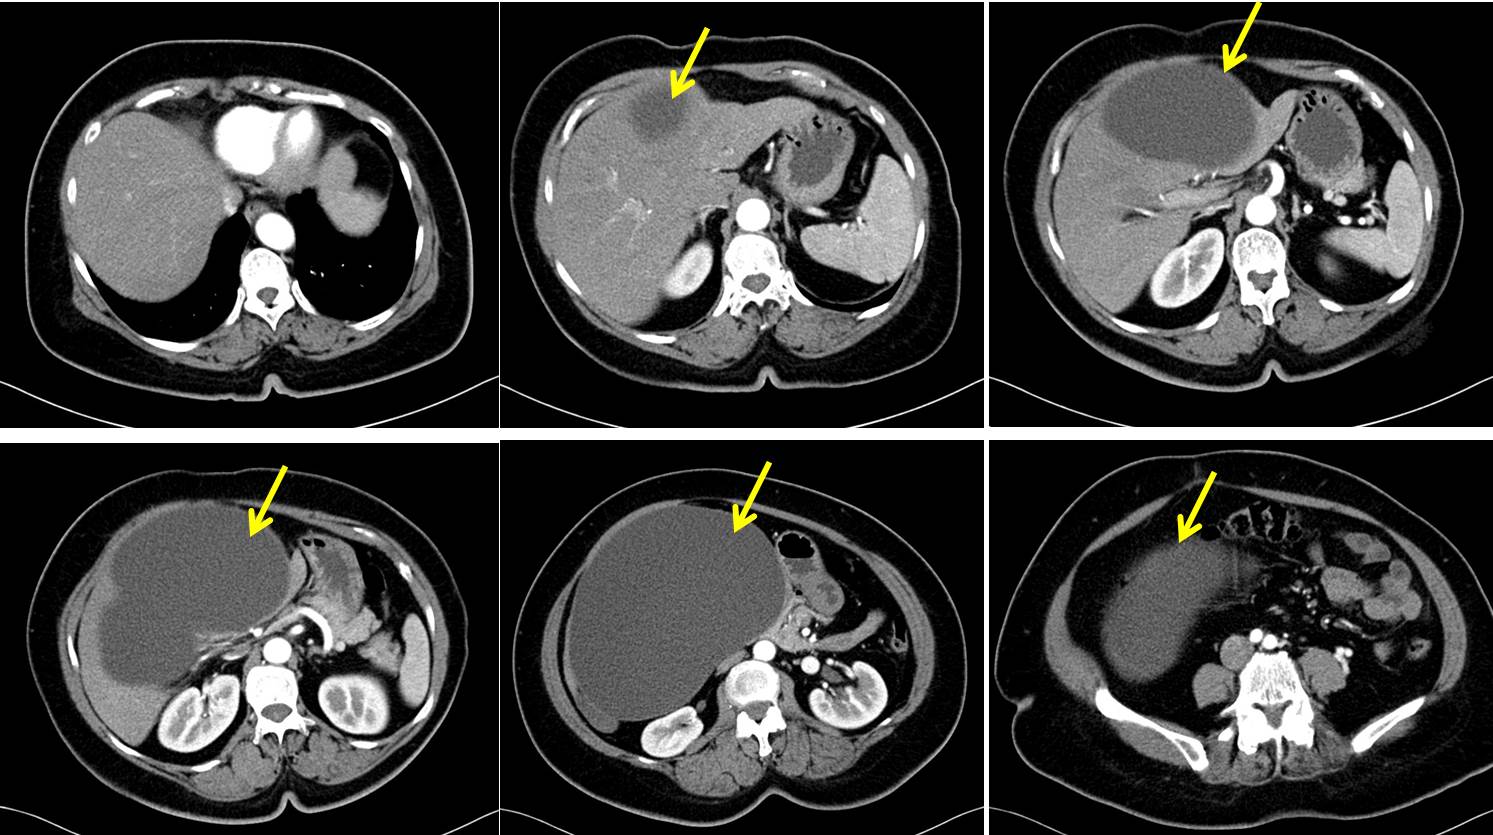

Malignant growth of the hepatic flexure (yellow arrow) with extensive What Is Malignant Neoplasm Of Hepatic Flexure — hepatocellular carcinoma (hcc) is the most common type of primary liver cancer. — chronic infection with the hepatitis b virus (hbv) or hepatitis c virus (hcv) increases your risk of liver cancer. Mendelson, md september 21, 2024. — short answer. The hepatic flexure is the bend. A large bowel stricture with shouldering at the hepatic. . What Is Malignant Neoplasm Of Hepatic Flexure.

From www.wisegeek.org